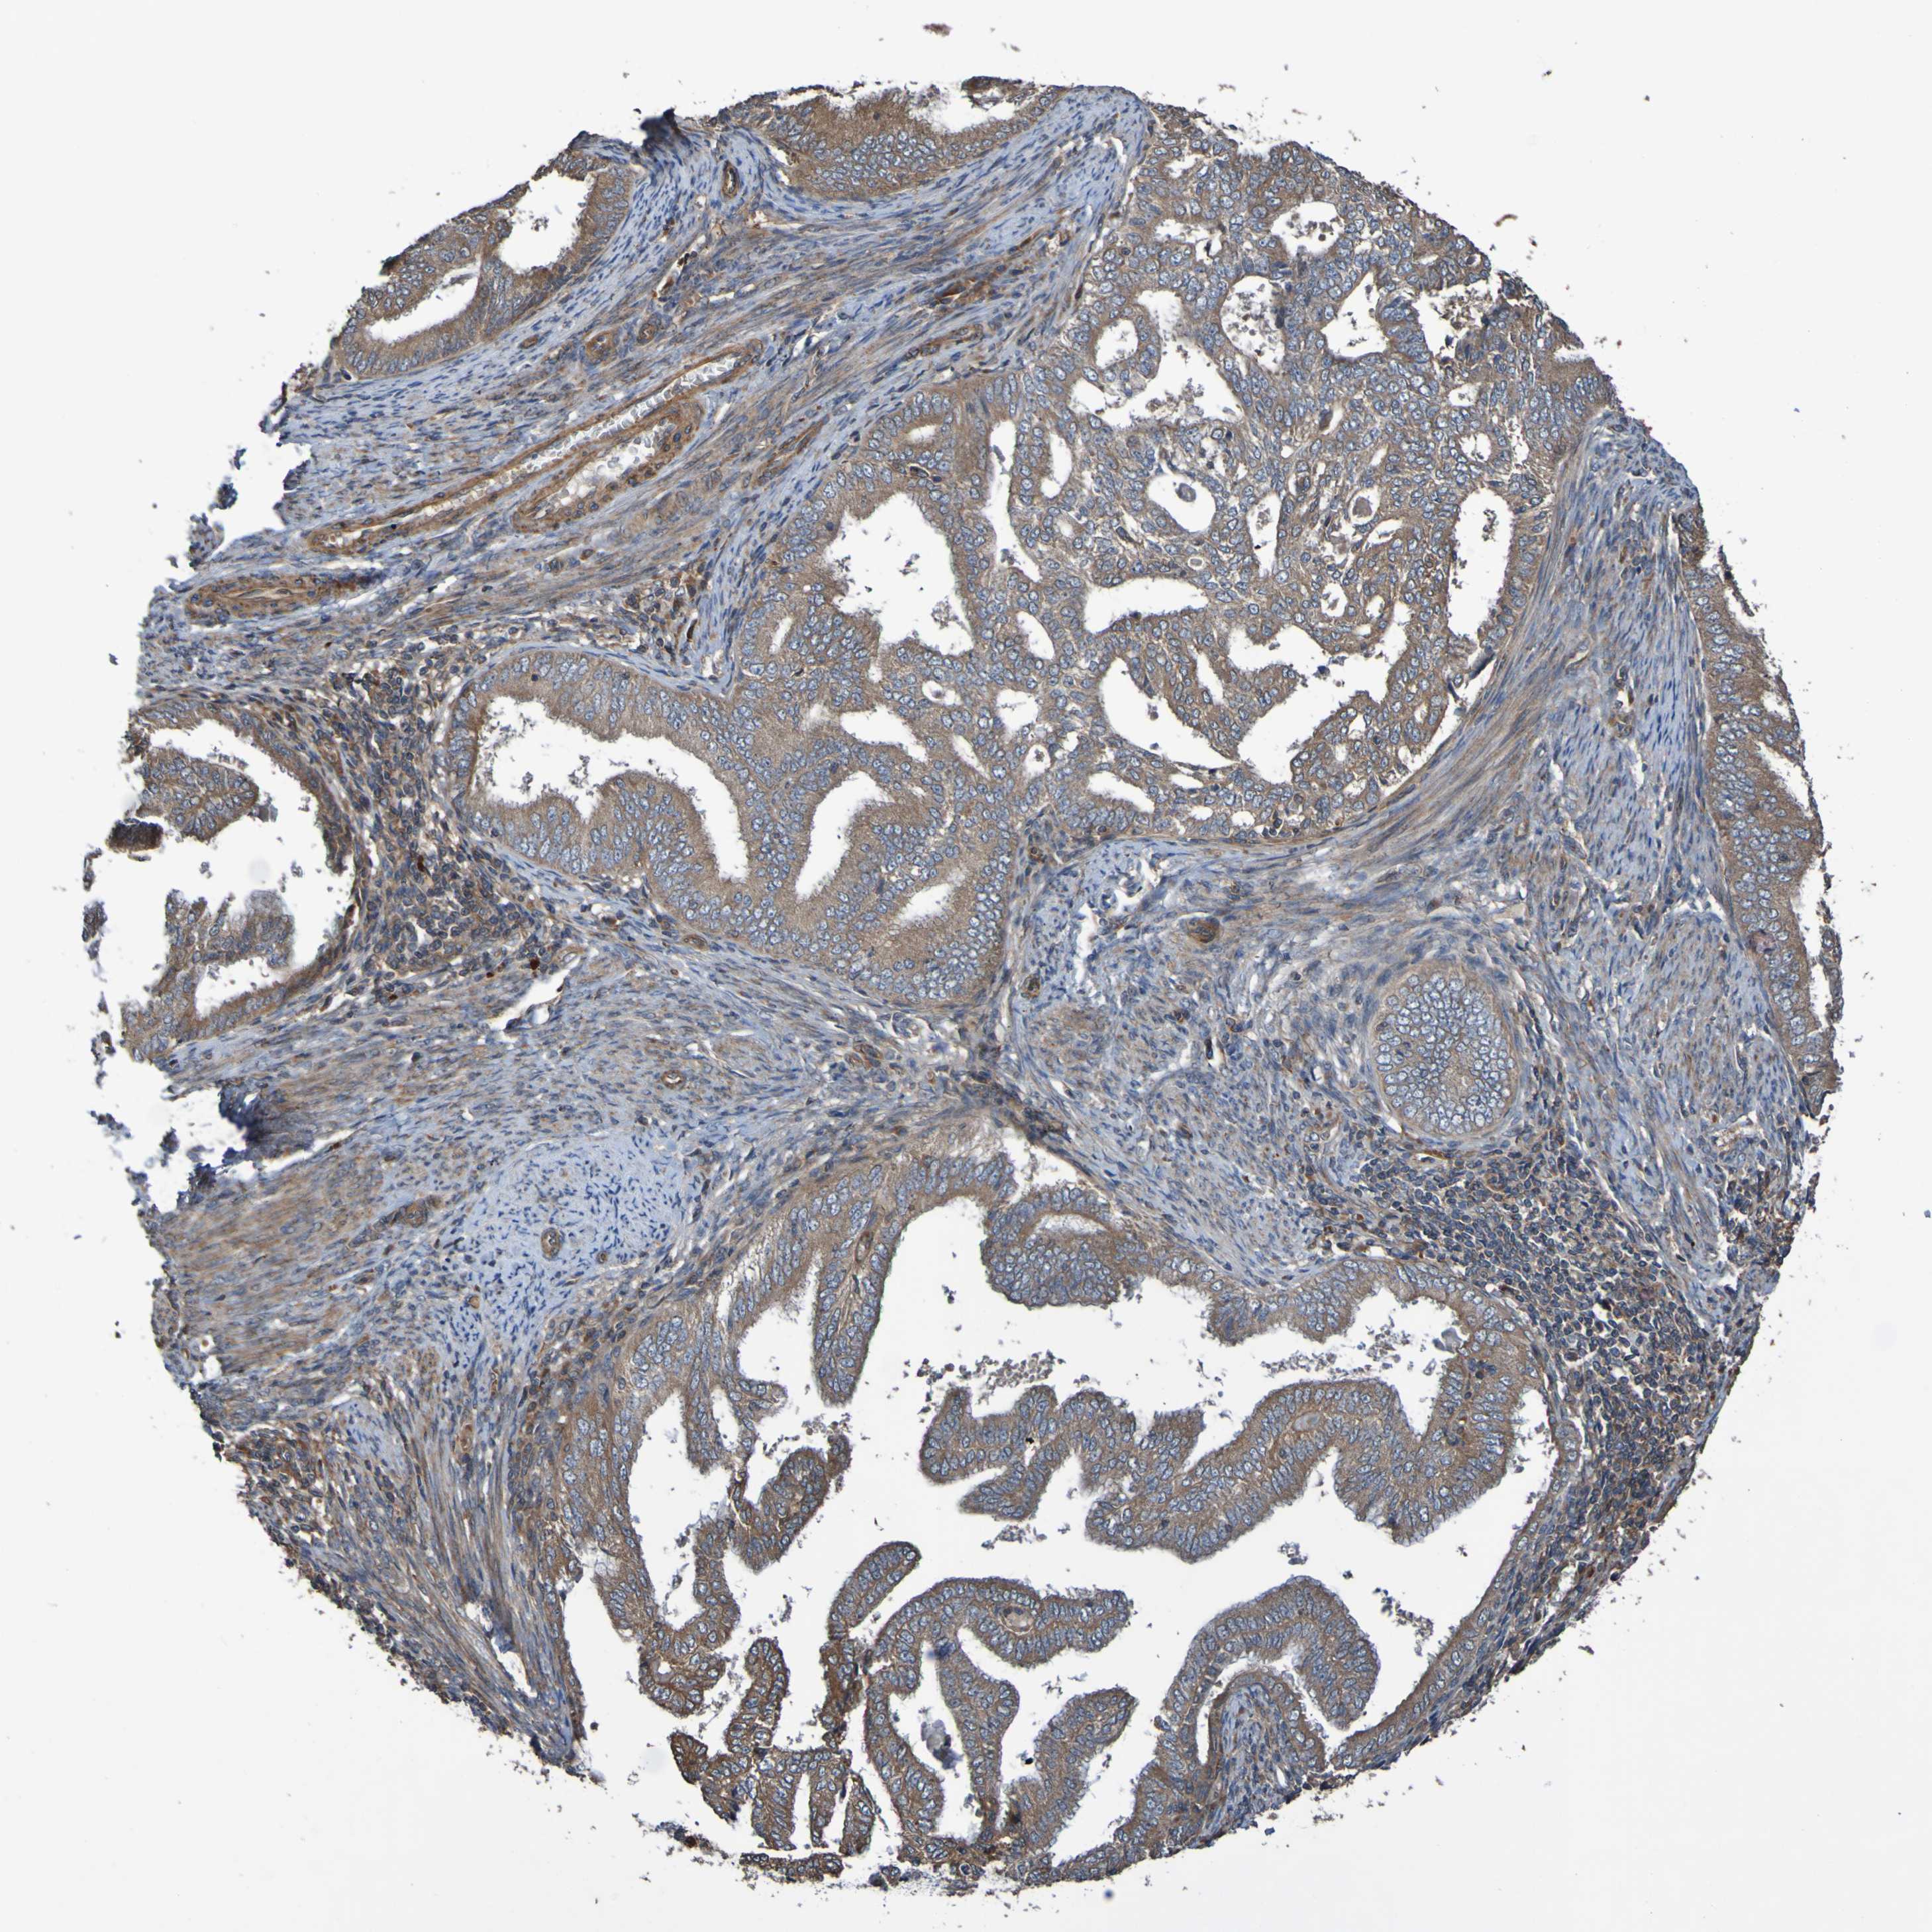

ENDOMETRIAL CANCER - Protein expressioni

A mouse-over function shows sample information and annotation data. Click on an image to view it in a full screen mode. Samples can be filtered based on level of antibody staining by selecting one or several of the following categories: high, medium, low and not detected. The assay and annotation is described here.

Note that samples used for immunohistochemistry by the Human Protein Atlas do not correspond to samples in the TCGA dataset.

Antibody stainingi

Antibody staining in the annotated cell types in the current human tissue is reported as not detected, low, medium, or high, based on conventional immunohistochemistry profiling in selected tissues. This score is based on the combination of the staining intensity and fraction of stained cells.

Each image is clickable and will lead to virtual microscopy that enables deeper exploration of all samples and also displays staining intensity scores, fraction scores and subcellular localization as well as patient and tissue information for each sample.

Antibody CAB010911

Staining

High

Medium

Low

Not detected

Intensity

Strong

Moderate

Weak

Negative

Quantity

>75%

75%-25%

<25%

None

Location

Nuclear

Cytoplasmic/membranous

Cytoplasmic/membranous,nuclear

Adenocarcinoma, NOS